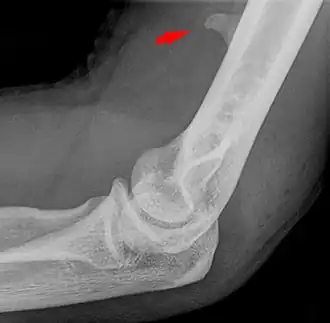

![]() Small supracondylar process seen on a lateral radiograph of the elbow | |

The supracondylar process of the humerus (also known as an avian spur) is a variant bony projection on the anteromedial aspect of the upper arm bone (humerus), about 5–6 cm above the medial epicondyle.[1] It is directed downward, forward and medially pointing to the medial epicondyle. A fibrous band, Struthers ligament, may connect this process to the medial epicondyle.[2] This variation has a prevalence of 0.68% and is significantly more common in women than in men.[3]